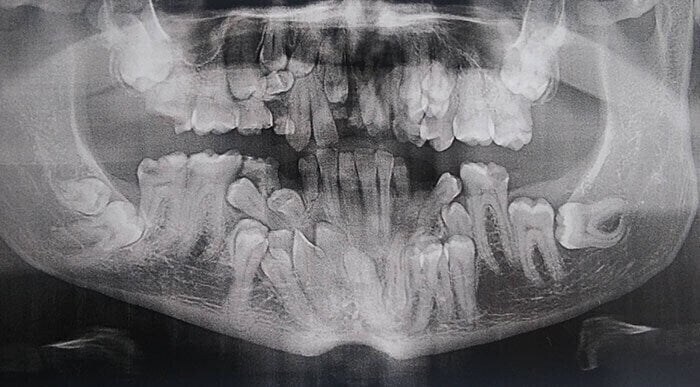

??? : 너 말 안듣고 나쁘게 굴면 저 아저씨 처럼 된다! Anonymous | 2025.11.12 15:22 | 조회 5 https://qquing.net/bbs/board.php?bo_table=humor&wr_id=1700807 주소 복사 이전글 다음글 랜덤 만화 목록 본문 저기 사진 보이니! 엄마 말 안들면 저렇게 된다. 추천 0 비추천 0